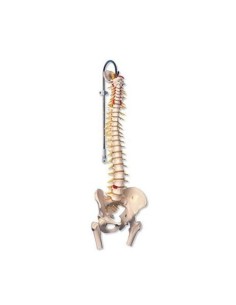

3B Scientifique, Colonne vertébrale de luxe peinte de façon classique avec troncs de...